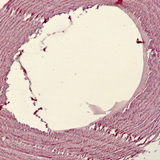

Λείοι μύες και ενδοθηλιακά κύτταρα σε αορτή περιστεριού

50x zoom